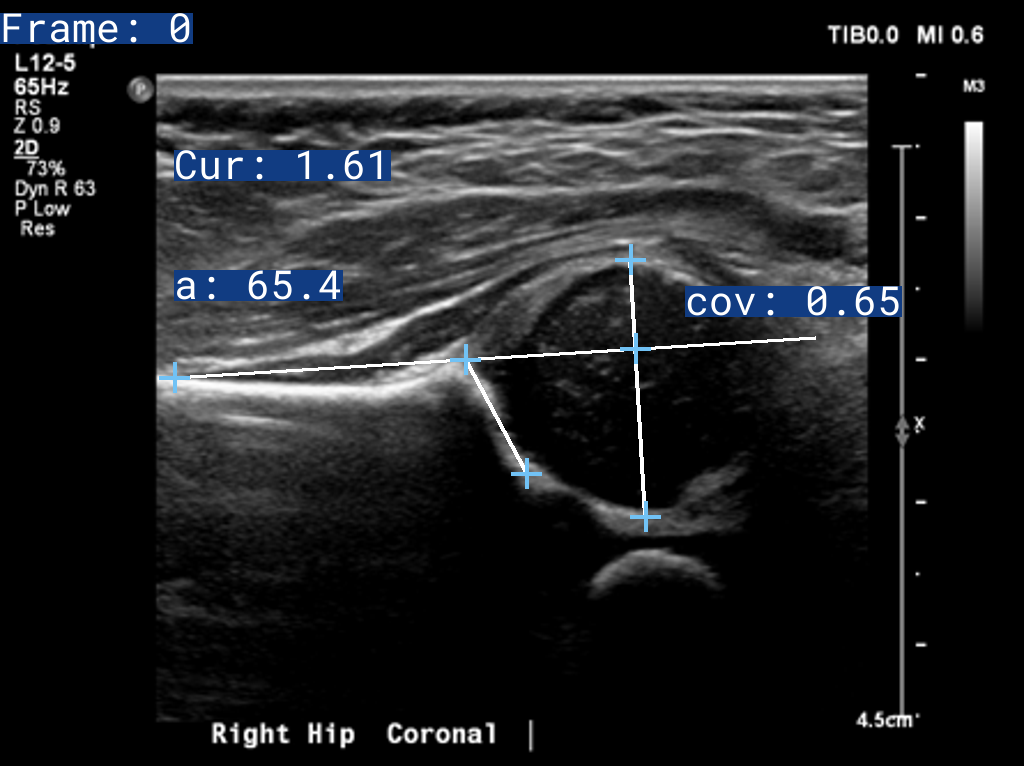

Retuve (from the scottish gaelic Ri taobh meaning beside) is a framework for analysing infant hips. It is designed to be a flexible and extensible framework that can be used by developers, AI researchers and clinicians.

It takes in raw hip Ultrasound and X-Ray images, and outputs a report with the labelled images, and the results, exactly as a clinician would.

Attribution of the above Ultrasound Images: Case courtesy of Ryan Thibodeau from https://radiopaedia.org 172535 (https://radiopaedia.org/cases/172535)